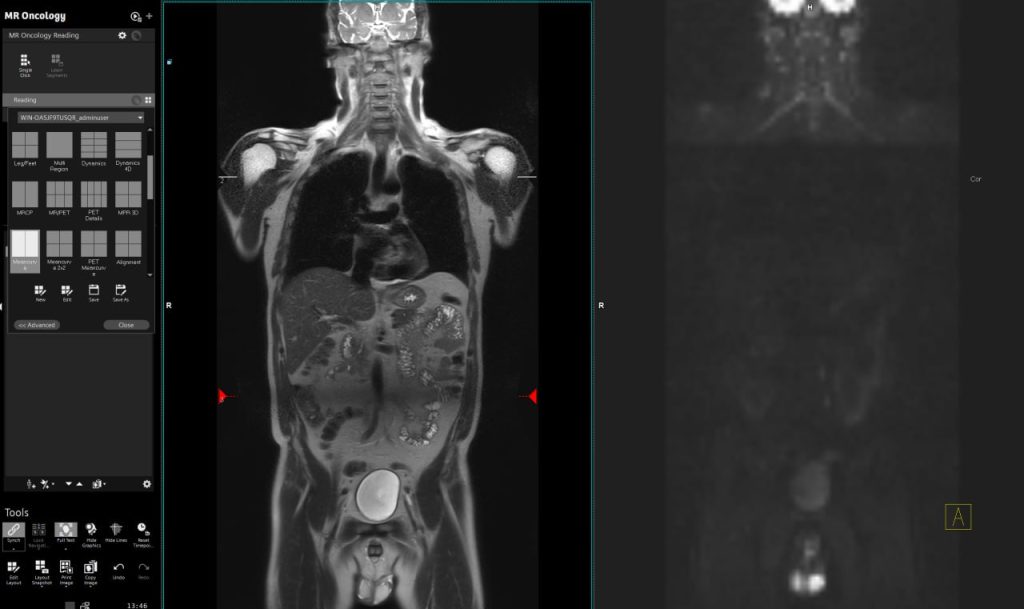

Як виглядає МРТ всього тіла?

На знімках нижче, ви можете побачити приклад МРТ всього тіла: